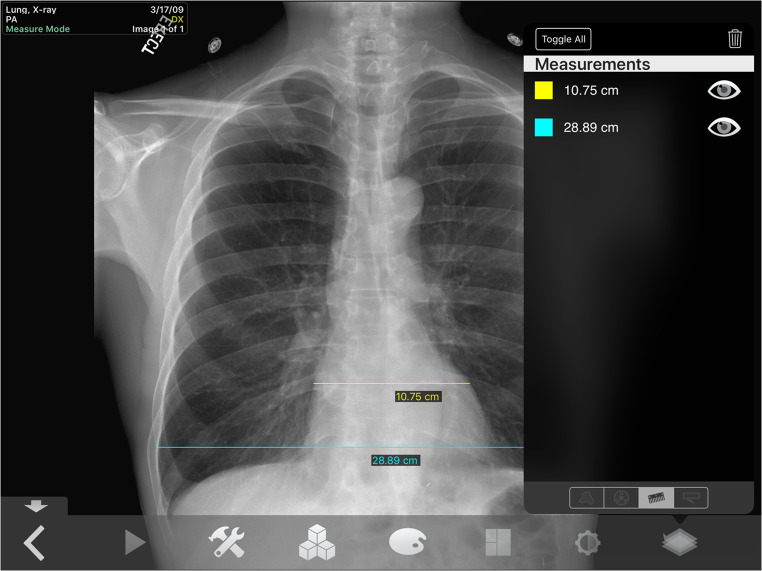

Measure—Digital ruler measures the length from point A to point B in centimeters. All measurements can be viewed at once and deleted one by one within the Overlays tab (Fig. 2).

Fig. 2.

Manipulation of the measure tool. Lung X-ray image set. The figure demonstrates an example of using the measure tool during image analysis to measure the cardiothoracic ratio of the cardiac silhouette